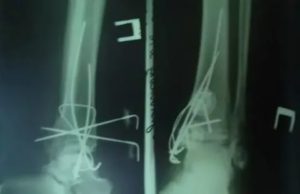

Если закрытое сопоставление провести не удается, необходимо хирургическое вмешательство. Желательно, чтобы оно было проведено через несколько дней после травмы. Для фиксации применяются винты, спицы. Рана ушивается, и устанавливается дренирующая система. Пациенту накладывают гипс и назначают противомикробные препараты.

Если кости уже срослись неправильно, то внутреннее вмешательство назначается планово. Выполняют разрез по наружной и внутренней поверхности голени. Выделяют костные отломки, производят их сопоставление и фиксацию металлоконструкцией (пластиной, винтами). В конце операции устанавливают специальный дренаж, накладывают гипс и назначают курс приема антибиотиков.

Гипсовую повязку нужно носить в течение 6 недель. В это время следует пользоваться костылями для ходьбы, начинать нагружать конечность можно только с разрешения врача.